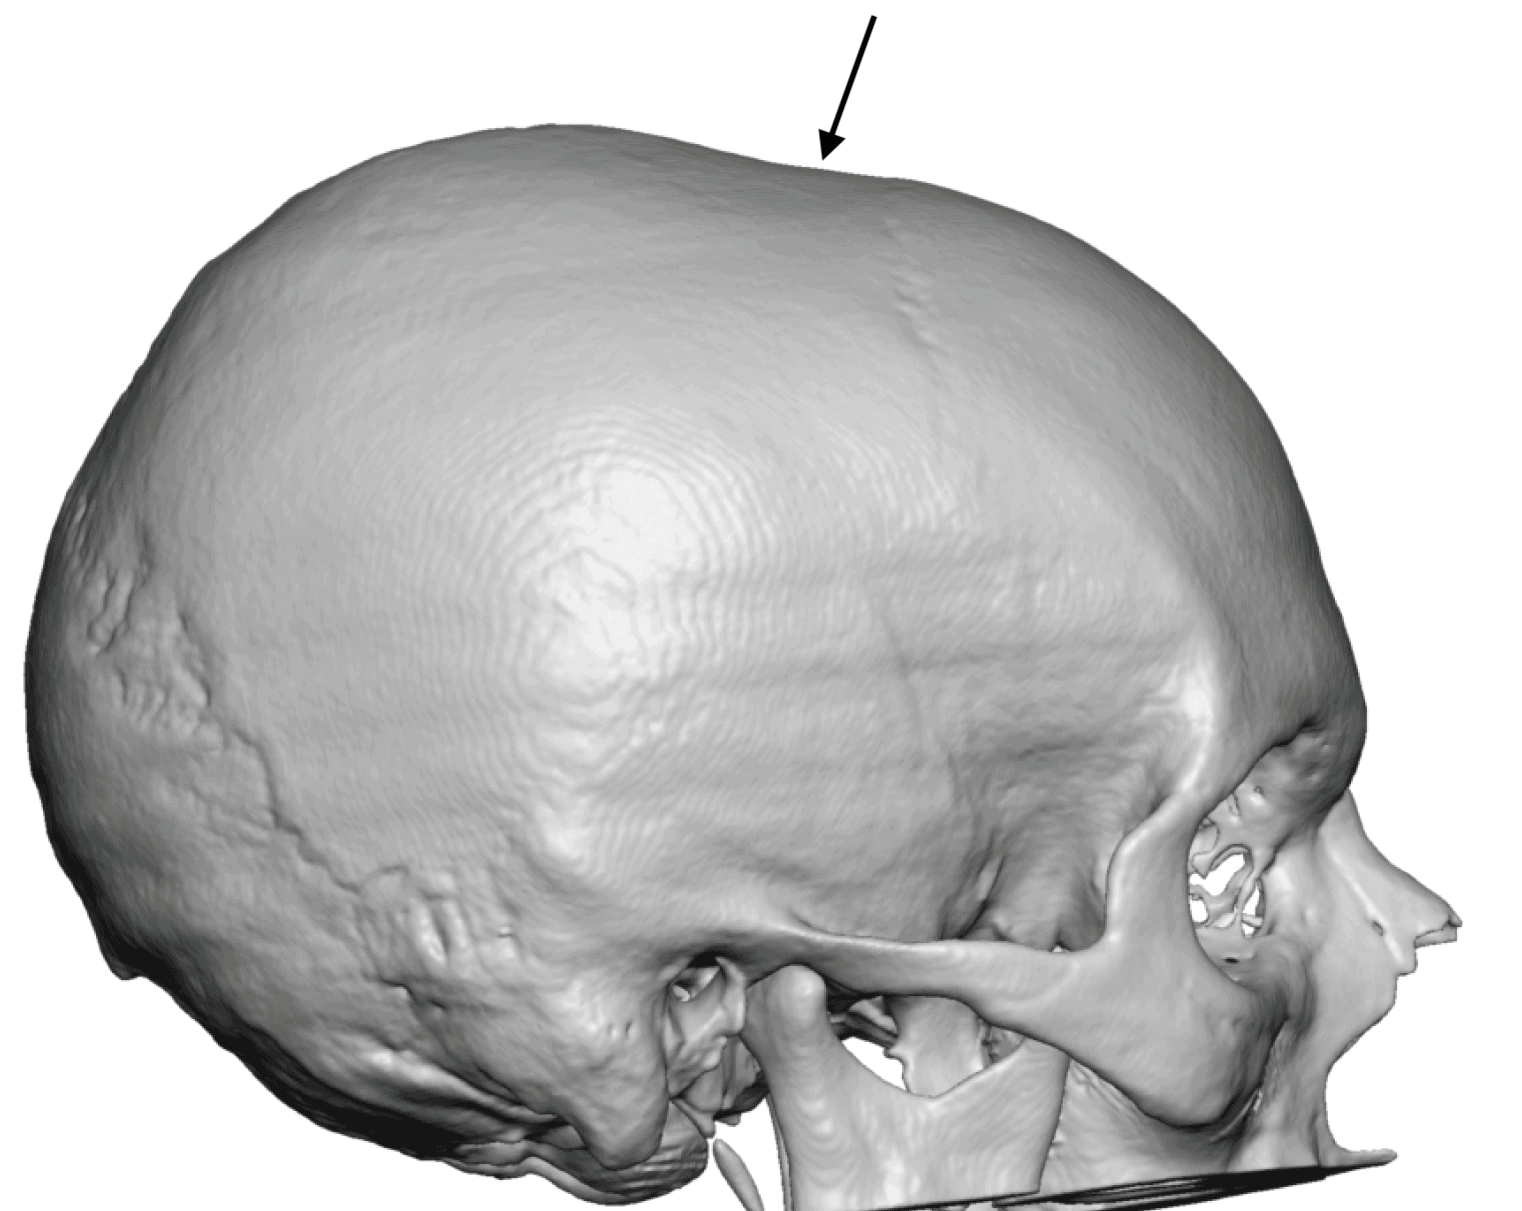

Patient 49

Desire for further skull augmentation after a primary skull implant.

Five years after an initial custom skull implant placement a new custom skull implant that increased the volume by 35% was placed.

Desire for further skull augmentation after a primary skull implant.

Five years after an initial custom skull implant placement a new custom skull implant that increased the volume by 35% was placed.